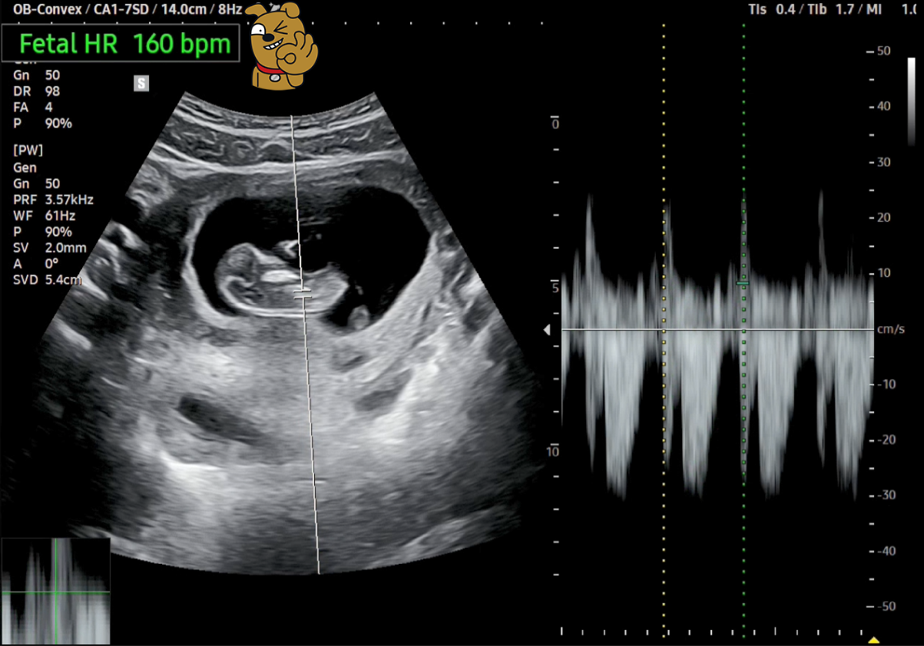

전원한 병원에서 다시 초음파 검사를 한 모양입니다. 딸애로부터 카톡으로 동영상이 전달되었습니다.

인터넷을 찾아보니 11주 차 태아의 크기는 약 4.1cm라고 하는데, 우리 '팡팡이'는 4.72cm로 자기 주수보다는 좀 더 자랐다고 합니다. 심장 박동수도 160 bpm으로 정상범위 내에서 잘 뛰고 있다고 하네요.

[11주 차 태아 크기(왼쪽), 심장 박동수(오른쪽)]

하지만 아쉽게도 지금은 자고 있어서 움직이는 모습은 보이지 않습니다.